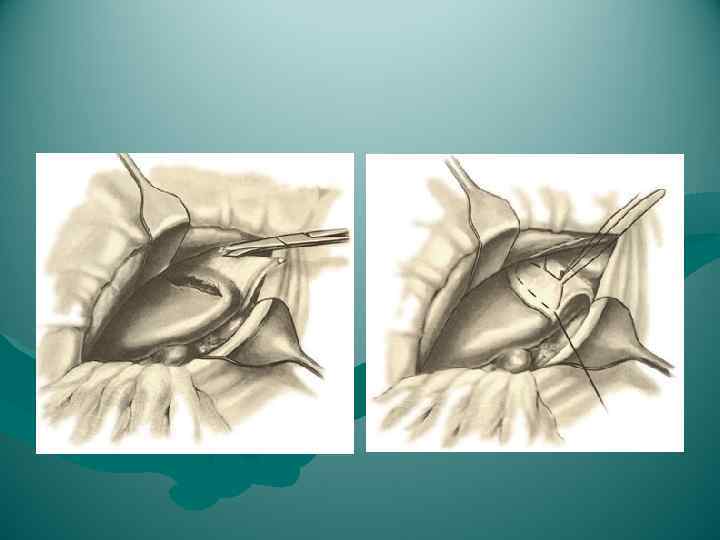

Раздавливание печени

Раздавливание печени

Резекция доли печени

Резекция доли печени

Перевязка левой печеночной вены.

Перевязка левой печеночной вены.